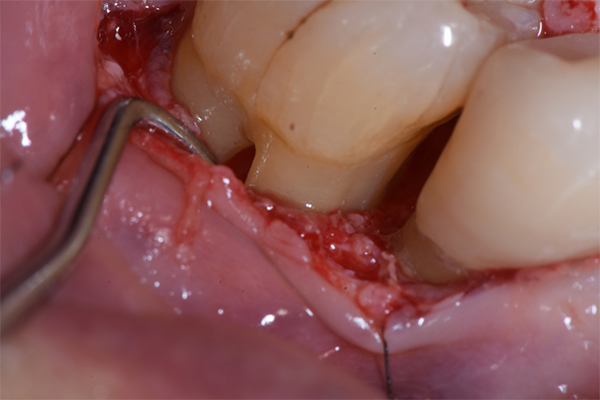

軽度〜中程度レベルの歯周炎であれば、ここで改善が見られますが、中程度以上の歯周炎の場合は、その後に歯周外科処置を行うことが多いです。なぜなら、歯周ポケットが5mm以上ある部位にSRPを行っても多くの歯石の取り残しがあるという報告があるため、深い歯周ポケットを有する患者さんに対しては歯周外科処置を行います。歯周外科処置で一般的な術式は歯肉剥離掻爬術です。痛く無いように麻酔(局所麻酔)をした後、歯肉をメスで切り(切開)、切った歯肉を骨から剥がし(剥離)、歯の根に付着した歯石、歯槽骨の形態などが直接見える状態で、歯石や感染物の除去を行います。その際必要であれば、その後に患者さん自身で清掃がしやすいように骨の形態を整える歯槽骨整形も行います。最後に切った部分を縫って(縫合)処置を終わります。